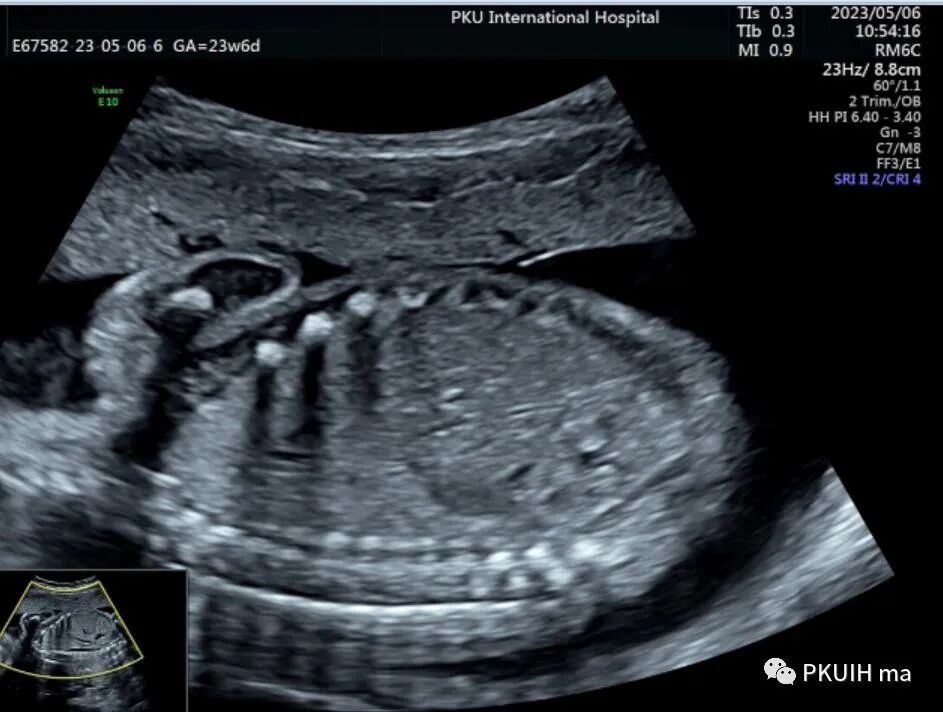

今天跟大家分享一个马蹄肾胎儿,23周常规系统排畸,矢状切发现胎儿肾脏偏长,下极边界相对不清晰,横断面发现肾盂有点轻度分离,但肾盂分离的方向有点不对劲,随仔细观察胎儿双肾。

双肾横断面观察双肾盂轻微分离,肾门指向腹侧,呈倒“八”字征。(LK:左肾,RK:右肾)

仔细观察双肾下极越过腹主动脉于腹主动脉和下腔静脉的前方相融合,同时肾的位置相对低,下极接近胎儿膀胱。(DAO:降主动脉,IVC:下腔静脉,BL:膀胱)